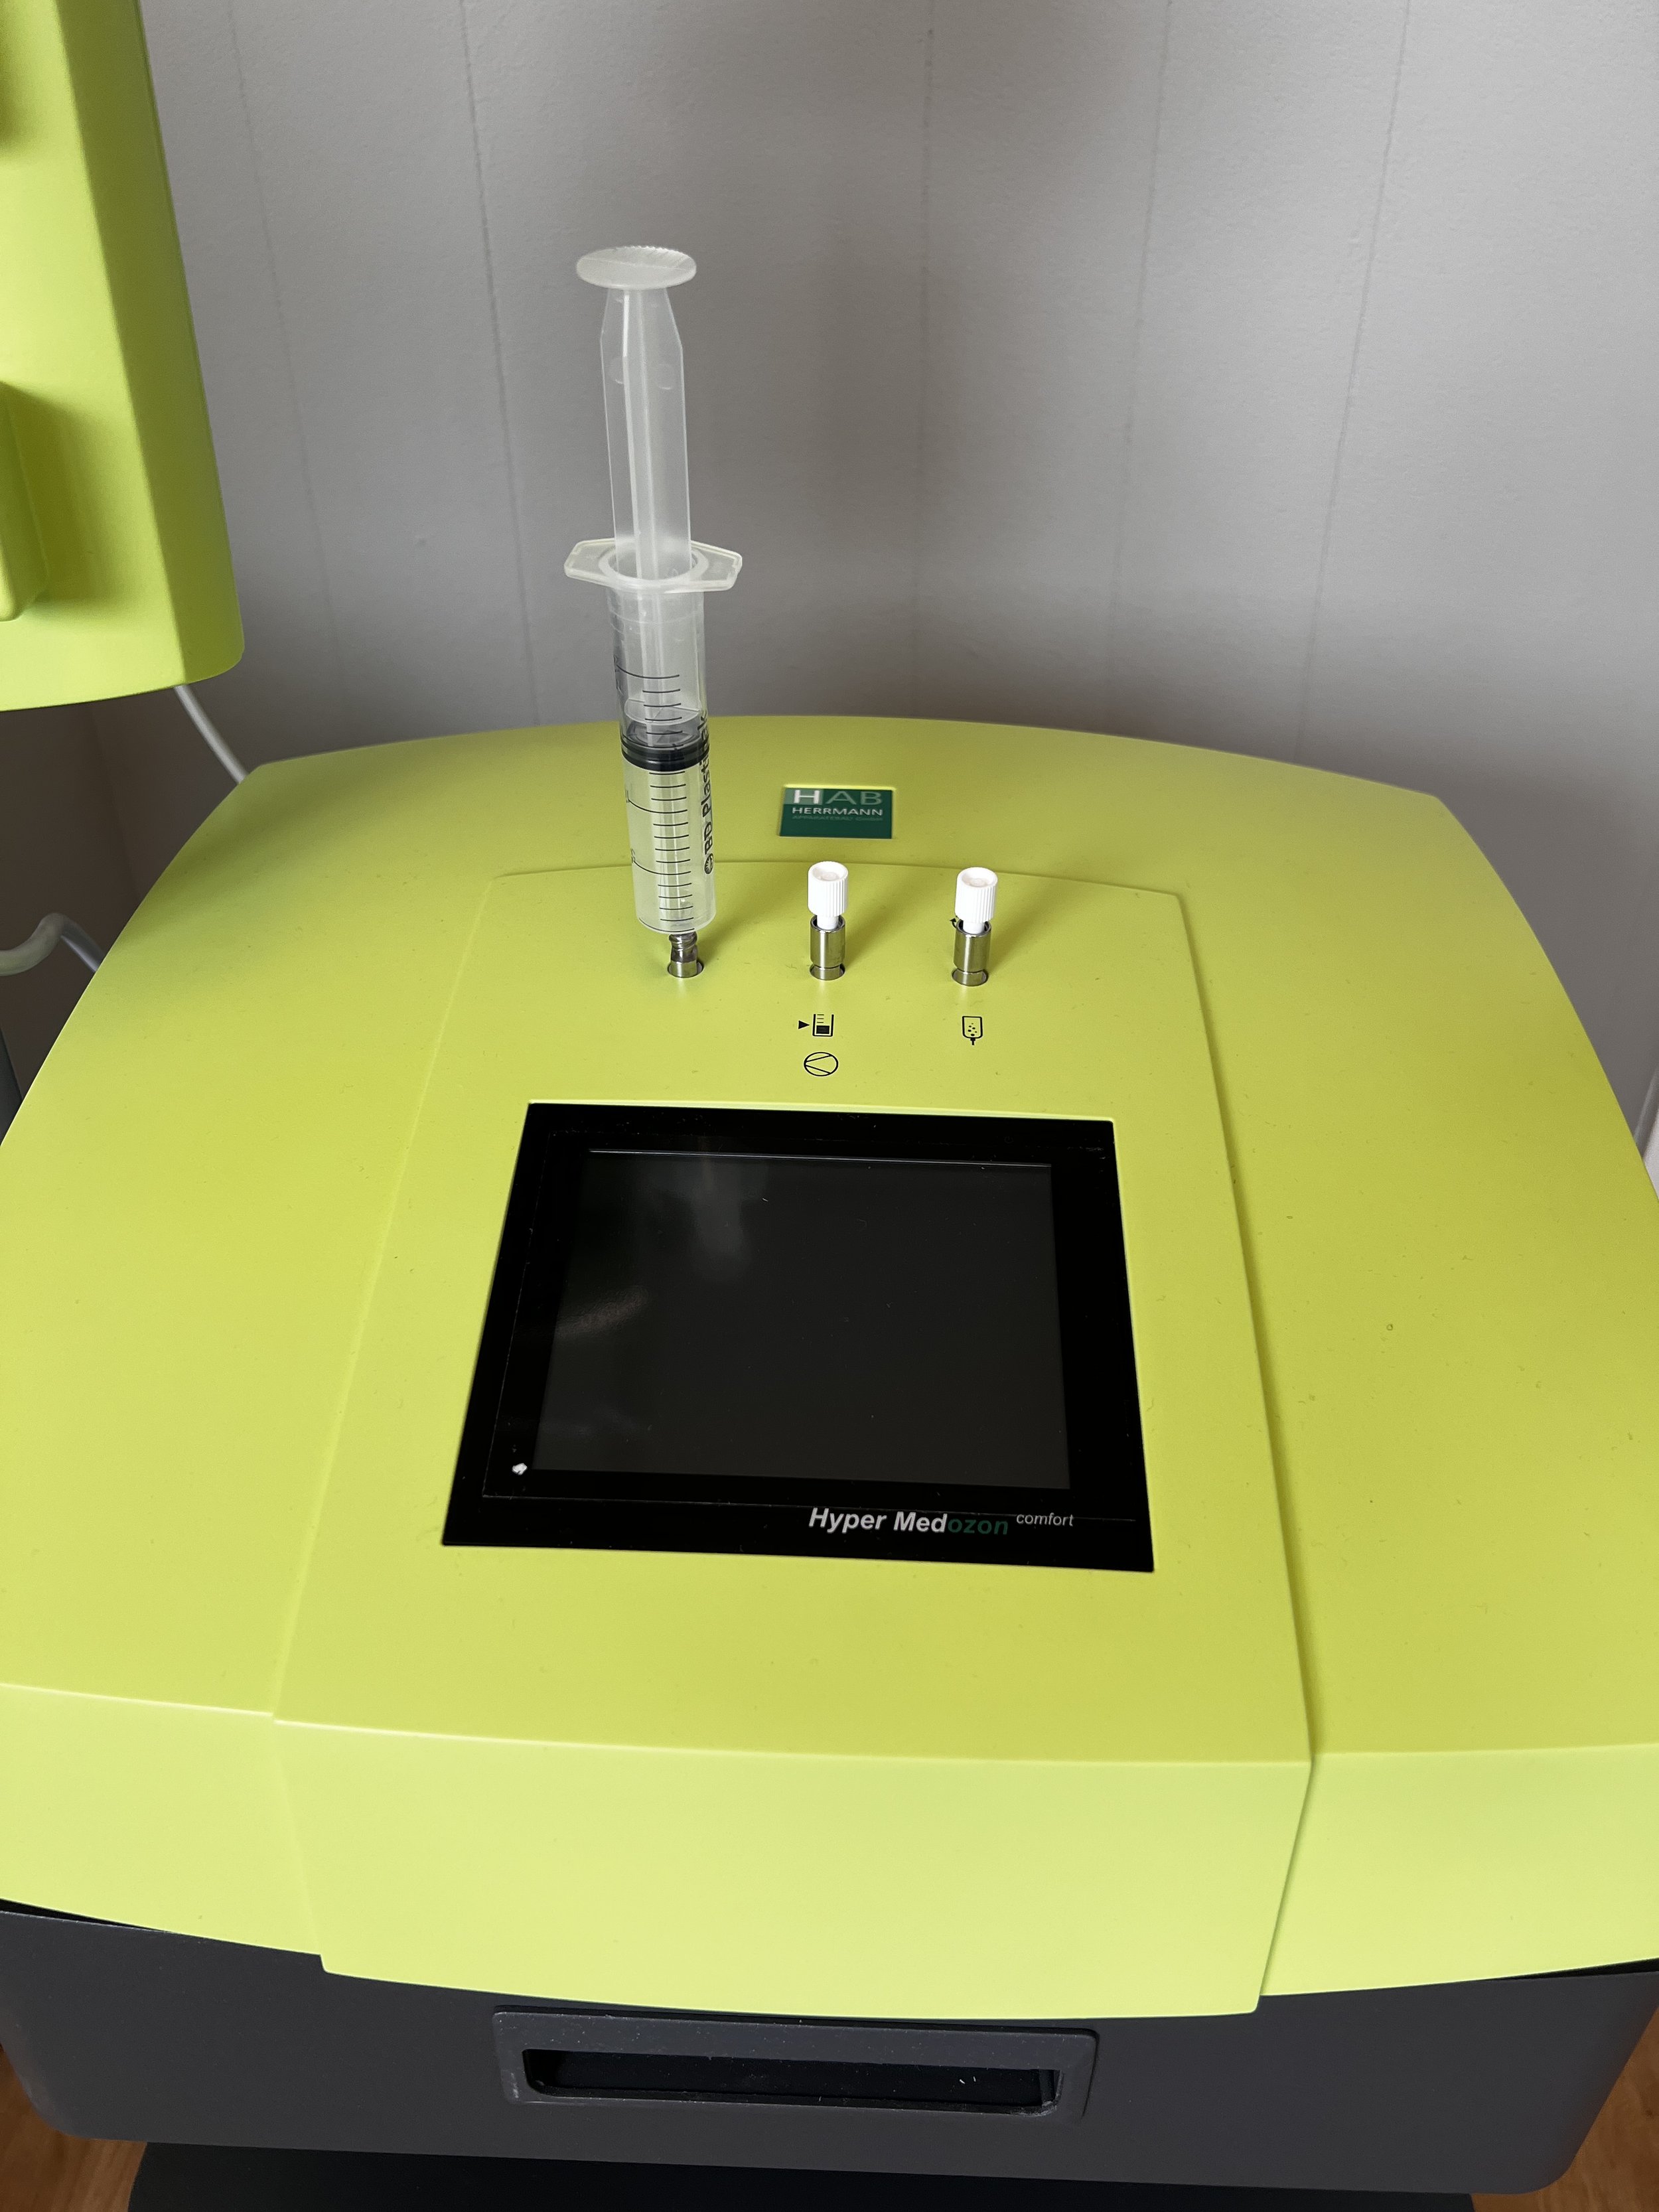

Prolotherapy & Prolozone: Pain Relief Where Other Methods Have Failed